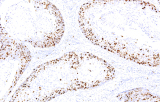

L’immunoistochimica (IHC) con anticorpi primari CE/IVD è essenziale per una diagnosi e classificazione accurata sia delle malignità ginecologiche che mammarie. Questi anticorpi consentono la rilevazione precisa di marcatori tumorali e proteine cellulari, supportando la diagnosi differenziale e guidando strategie terapeutiche personalizzate.

Gli anticorpi primari contro il recettore degli estrogeni (ER), recettore del progesterone (PR), HER2 e Ki-67 rimangono il pilastro della classificazione e delle decisioni terapeutiche nel cancro al seno. Questi anticorpi sono validati clinicamente e marcati CE/IVD per garantire una rilevazione affidabile e riproducibile dei biomarcatori – cruciale per guidare la terapia ormonale e le strategie di trattamento mirato.